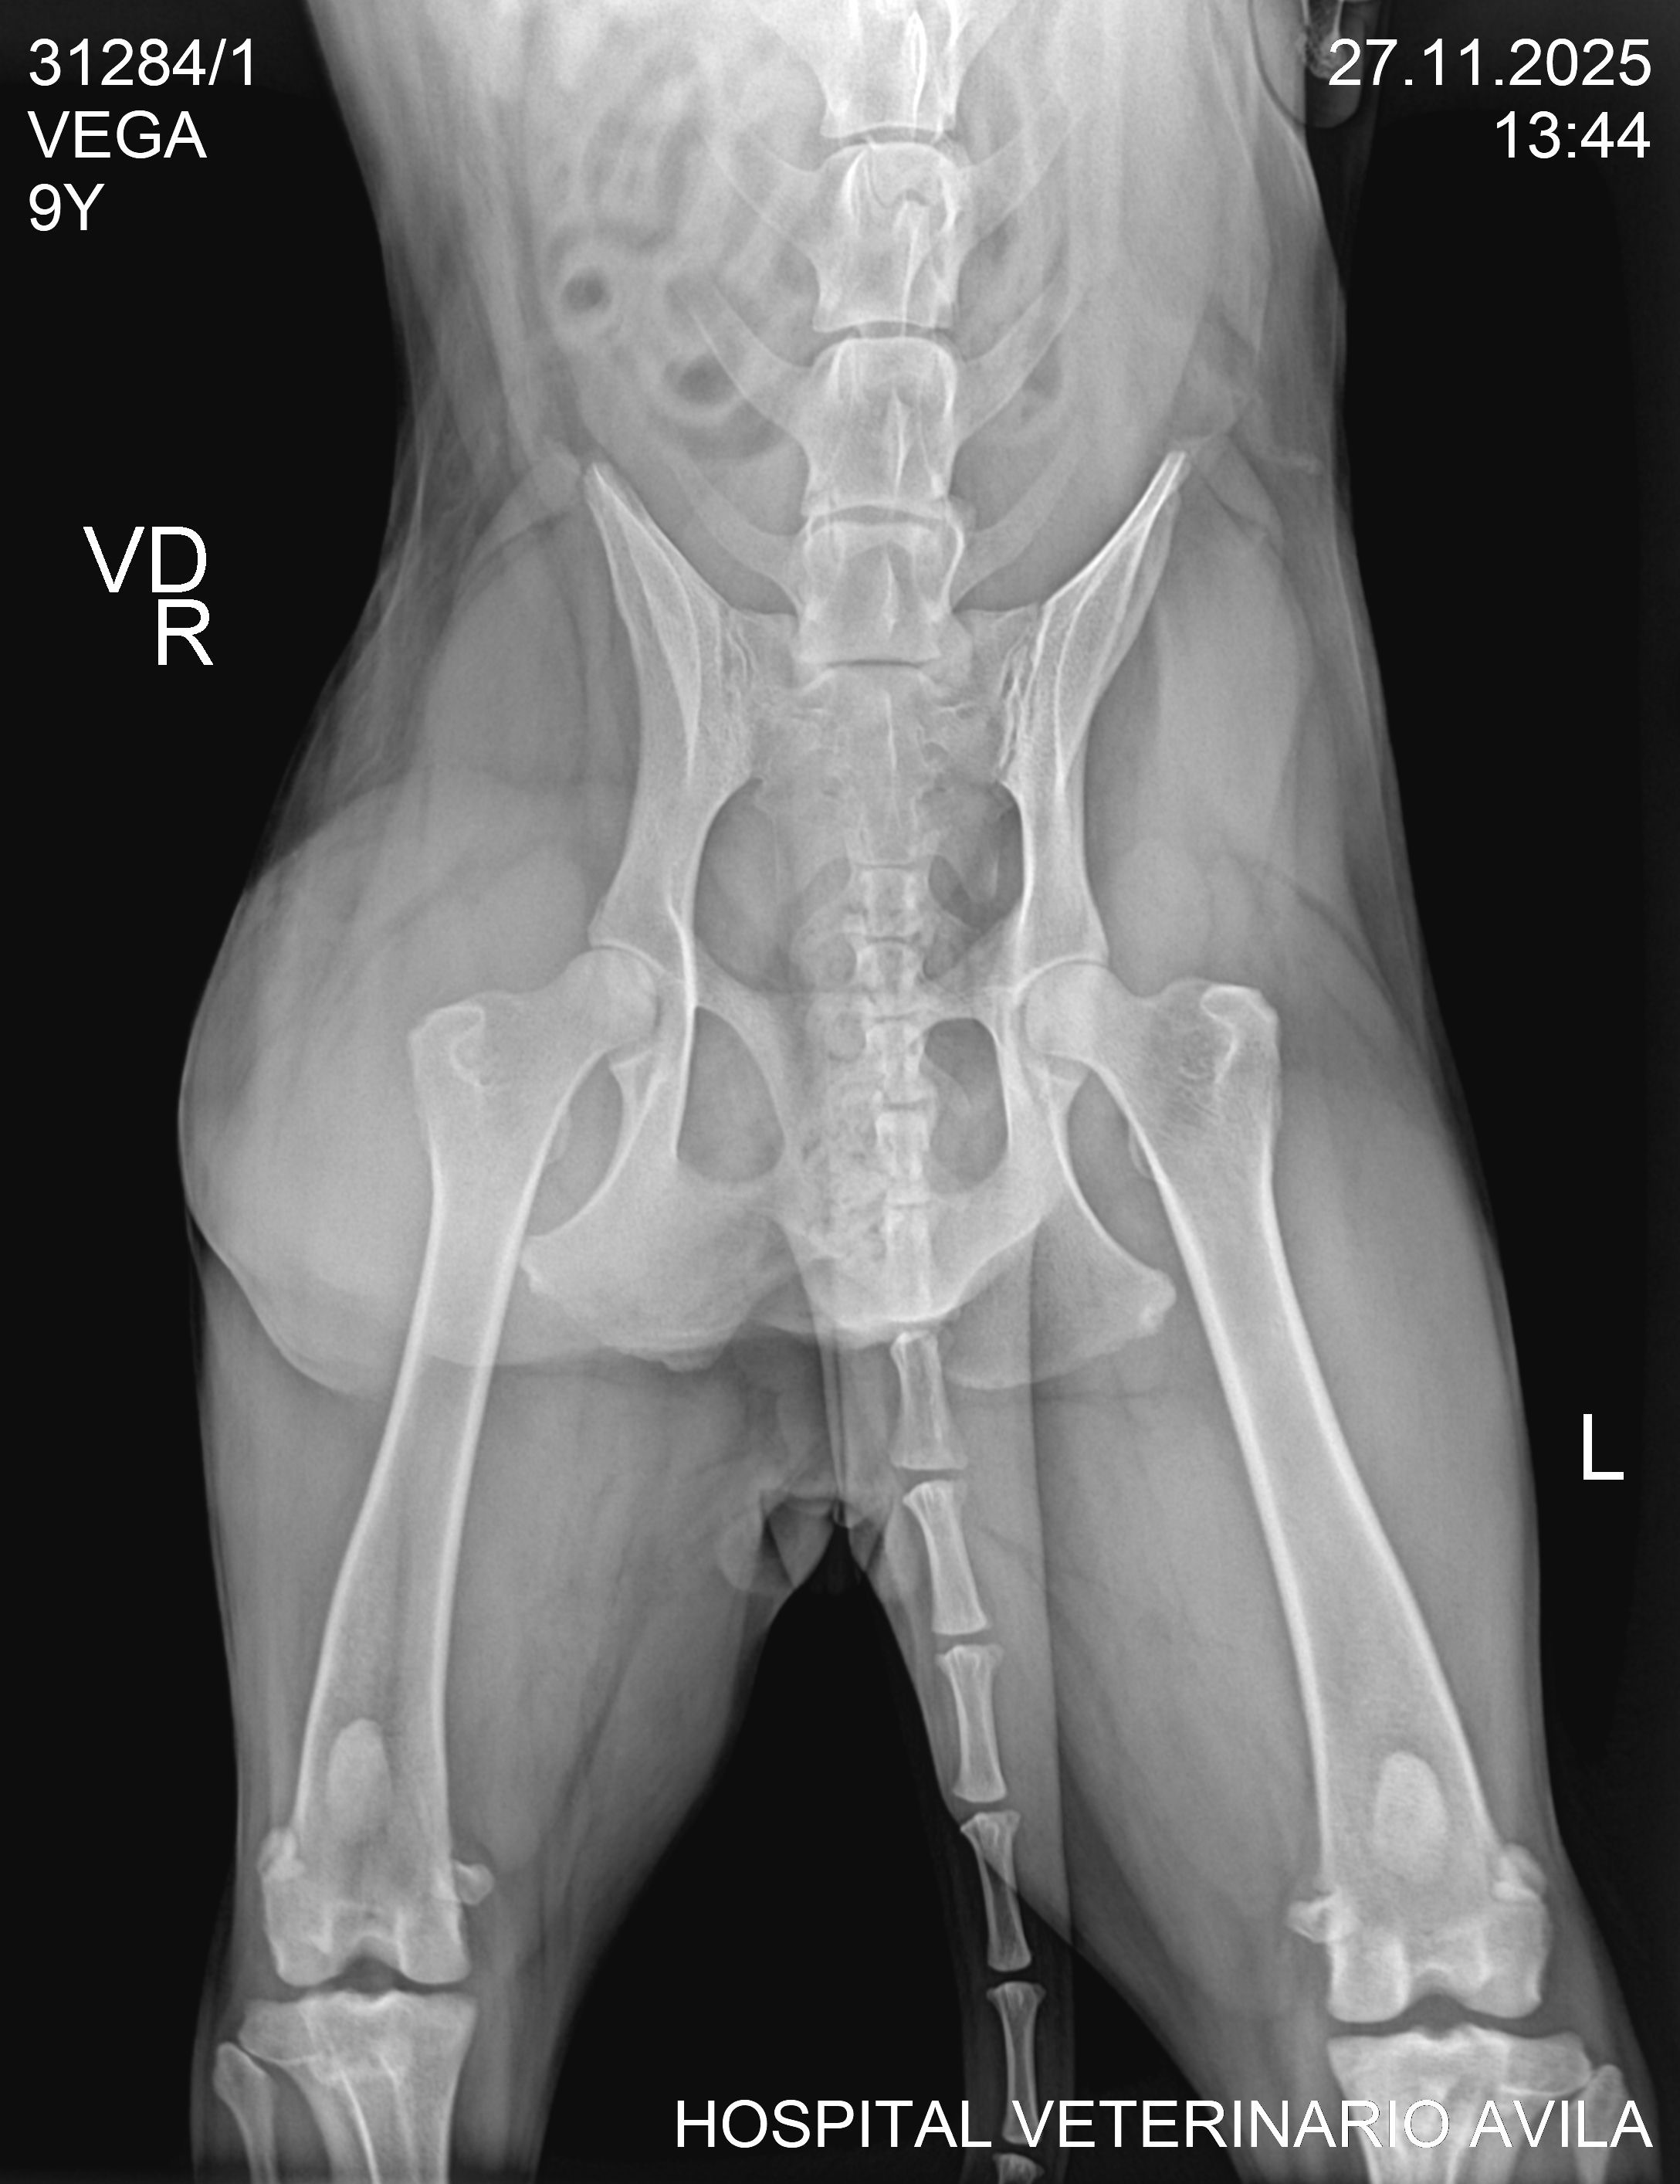

Vega has a cancerous tumor. Please help us raise funds for her surgery and electrotherapy so that we can give her a long life!

The surgery itself costs $500, plus the electrochemotherapy and follow-up medications. The veterinarian believes this treatment will work! We believe so too! Help us give her a fighting chance.